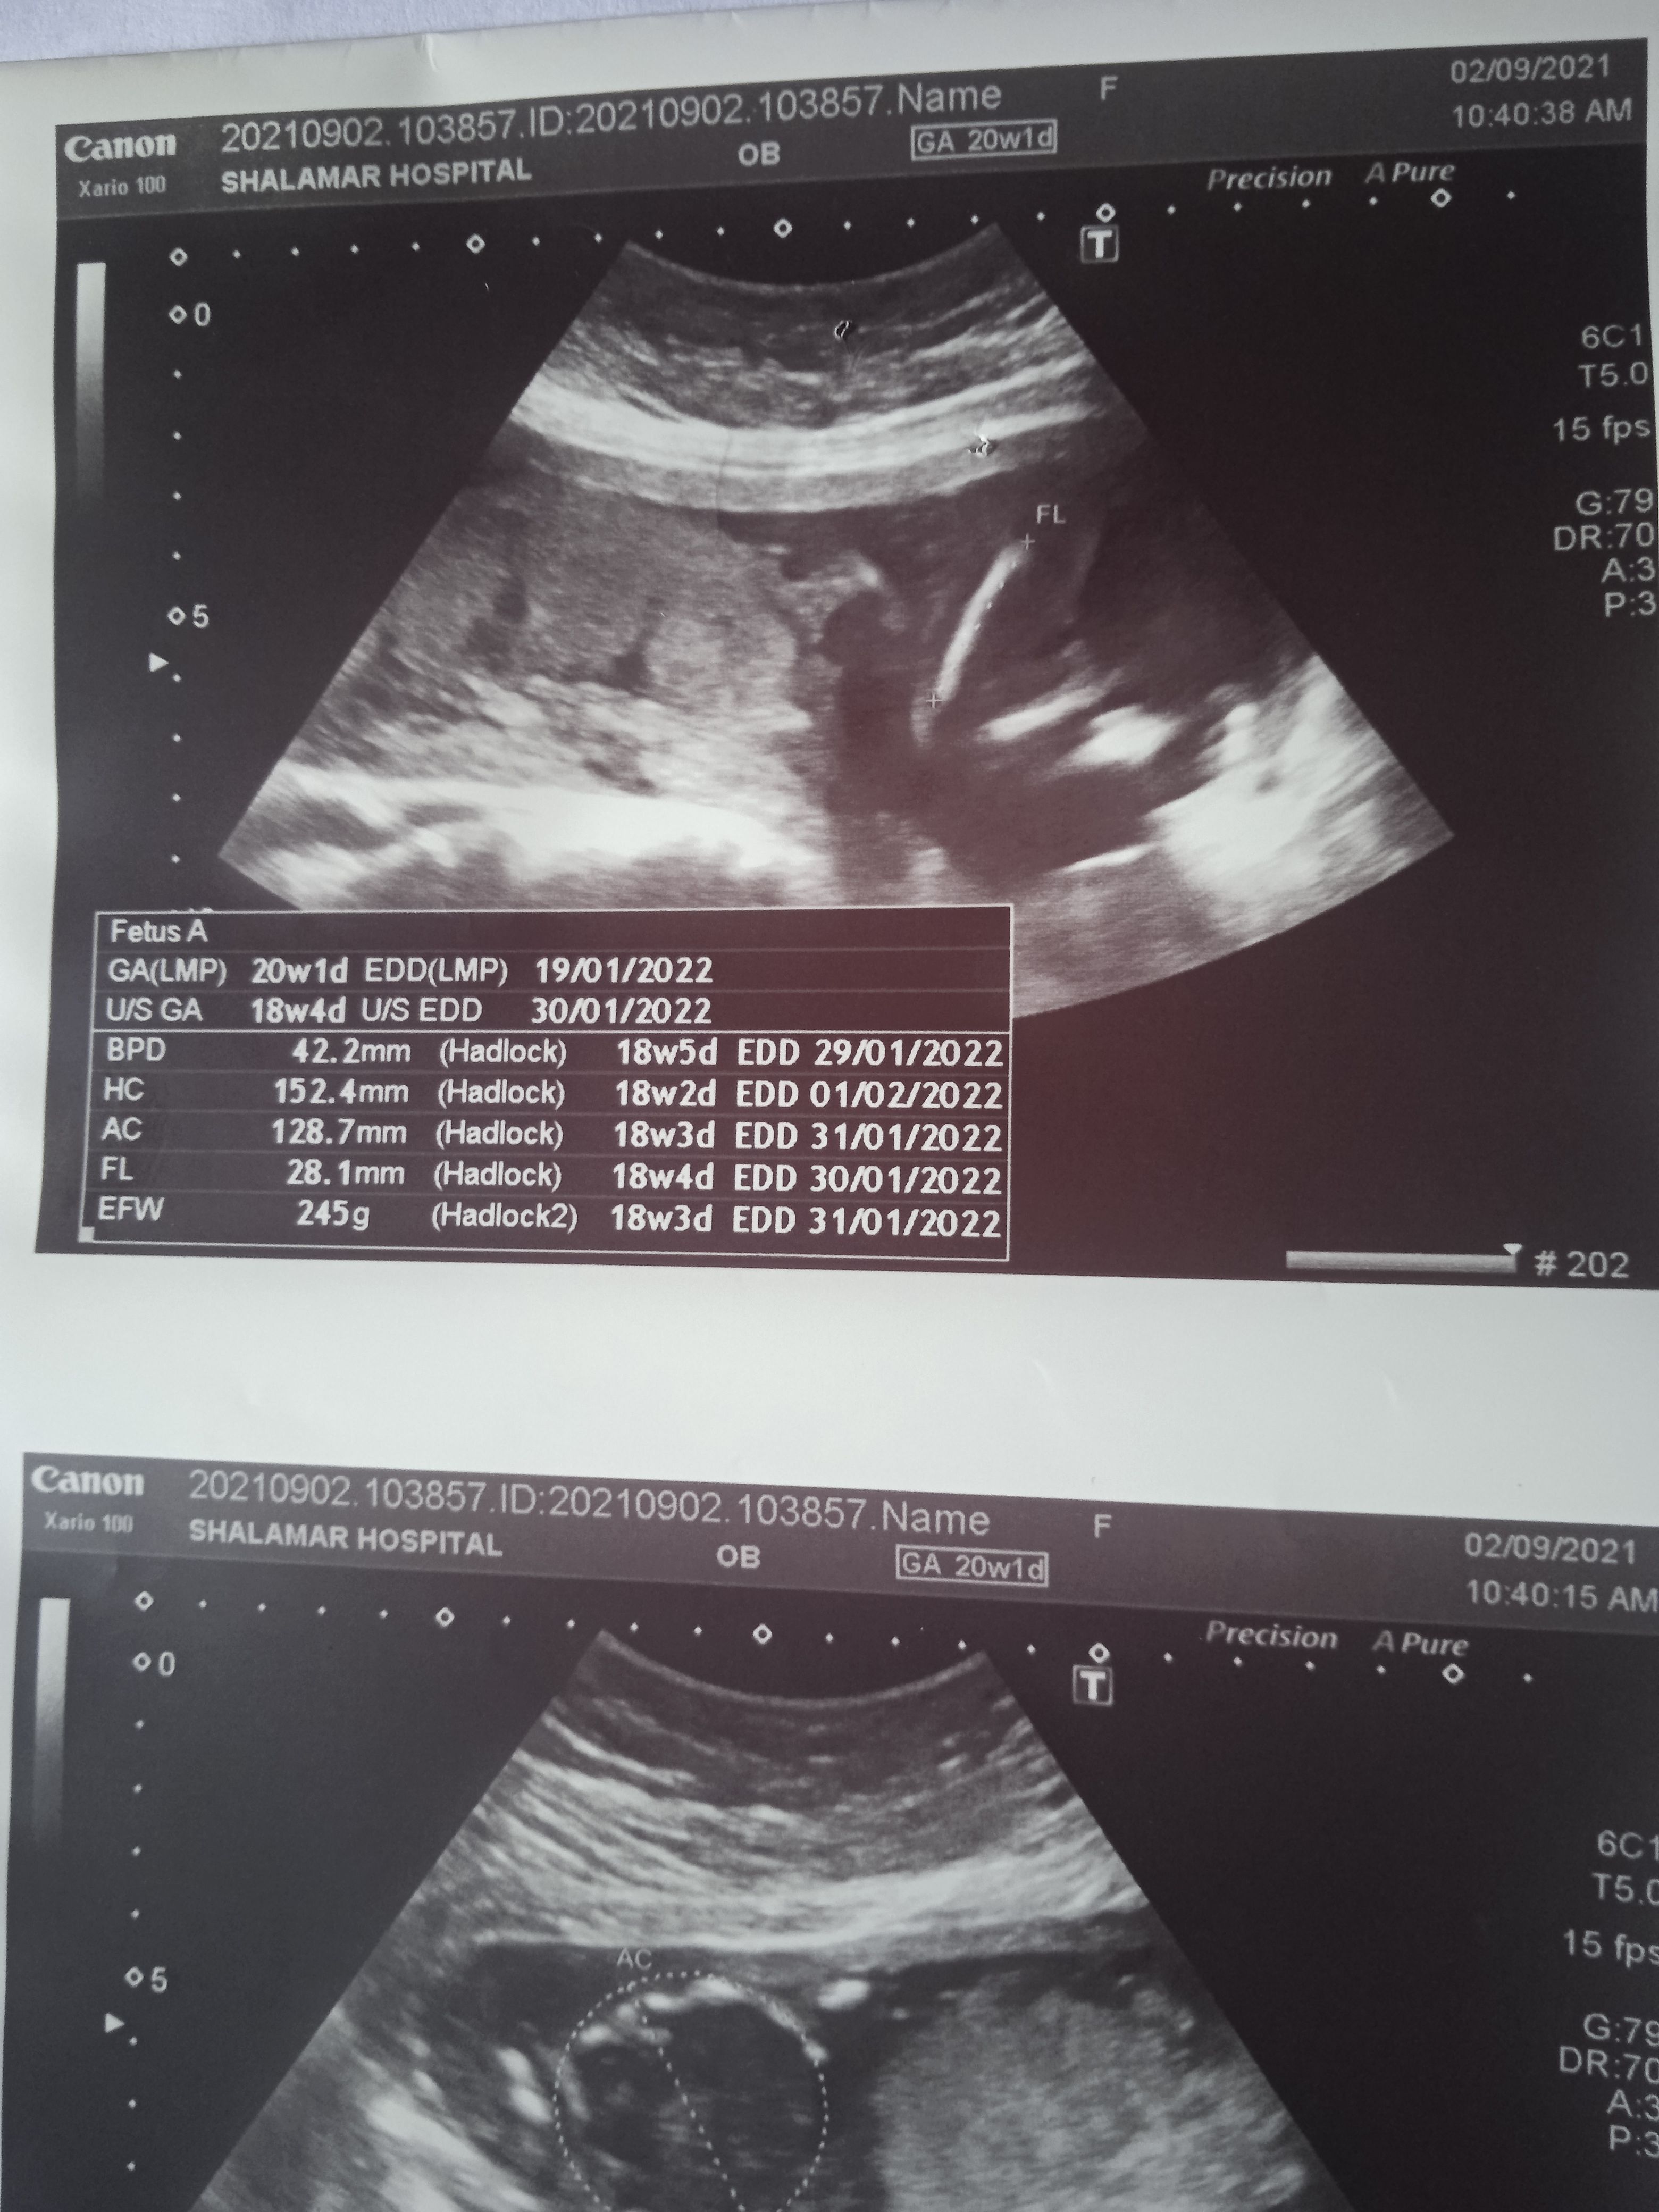

Please check the pics below.

And tell me about my baby gander.

Here is my altrasound report

Plz tell me gender of my baby plz

Here is altrasound report

Please see that report.

Anyone please let me know my baby's gender

I have uploaded my altrasound report